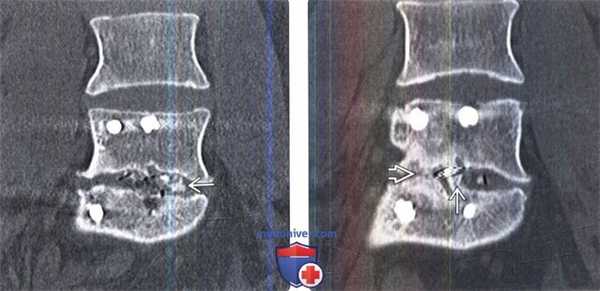

(Слева) КТ-картина вскоре после межтелового спондилодеза с использованием рентгеннегативного спейсера, заполненного костным пластическим материалом. Через три месяца после операции у этого пациента было отмечено появление ободков просветления вокруг металлоконструкций, свидетельствующее о некоторой дестабилизации фиксатора, и проседание межтелового спейсера, отражающее потерю им структурной стабильности. Через шесть месяцев отмечено появление костных мостиков снаружи от спейсера и внутри него. Кистозные просветления вблизи межтелового спейсера (МС) и линейные дефекты костных мостиков свидетельствуют о замедленной в данном случае консолидации.

(Справа) КТ через 12месяцев после операции: признаки костного сращение внутри и по периферии межтелового спейсера (МС).